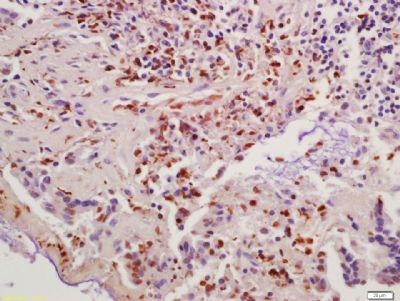

组织/细胞:人结肠癌;4%多聚甲醛固定和石蜡包埋;

抗原提取:柠檬酸缓冲液(0.01M,pH 6),15min煮沸,用3%过氧化氢阻断内源性过氧化物酶30min;37℃下阻断缓冲液(正常山羊血清,C-00 05)20 min;

孵育:抗Cyclin B1多克隆抗体,未结合(BS-057 2R)1:200,在4°C过夜,随后与二级抗体(SP-023)和DAB(C-00)染色结合。